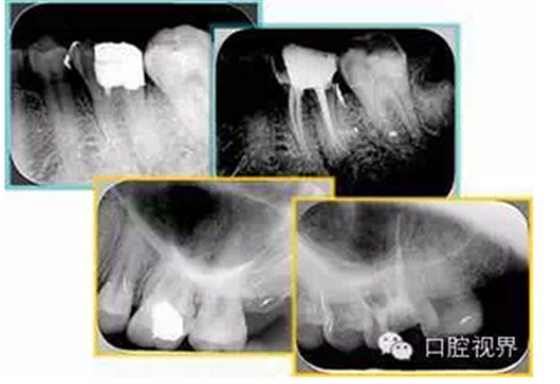

常見不良根管充填物有干髓、塑化、塑化 + 根充和不良根充。

( 1 )干髓。

干髓治療時,開髓后髓腔里注入甲醛甲酚 FC 灌髓,三聚甲醛固定,髓室底放置三聚甲醛緩慢釋放,進行根管無害化處理。髓腔緩慢壞死,機體代償出現(xiàn)根管鈣化。如果患者在封閉腔出現(xiàn)出現(xiàn)病變,由于髓腔鈣化,根管堵塞嚴重,檢查治療比較困難。

解決方法:1 )徹底去除壞死的牙髓組織。 2 )借助化學性藥劑,如 EDTA 等。3 )初銼選用8#或10#K 銼,平衡力法探察到工作長度 , H銼上下提拉法使根管擴大,提高工作效率。

左圖和上圖為干髓治療后牙齒,齲齒疏通后進行根管充填。

( 2 )塑化。

傳統(tǒng)的治療思維:塑化治療后患者需將塑化液清理干凈,達到徹底根管治療目的。

目前的治療思維:以前塑化治療效果好時不必清理干凈塑化液。對于根尖沒有病變的患者,可借助溶解劑建立通路;根尖存在病變的患者往往是塑化治療不理想患者,需要徹底打通通路。

( 3 )塑化 + 根充。

如圖為塑化加根充處理后牙齒 X 線片。